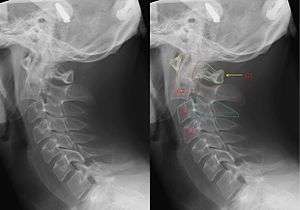

| X-ray of the cervical spine with a Hangman's fracture. Left without, right with annotation. Clearly can be seen that C2 (red outline) is moved forward with respect to C3 (blue outline). | |